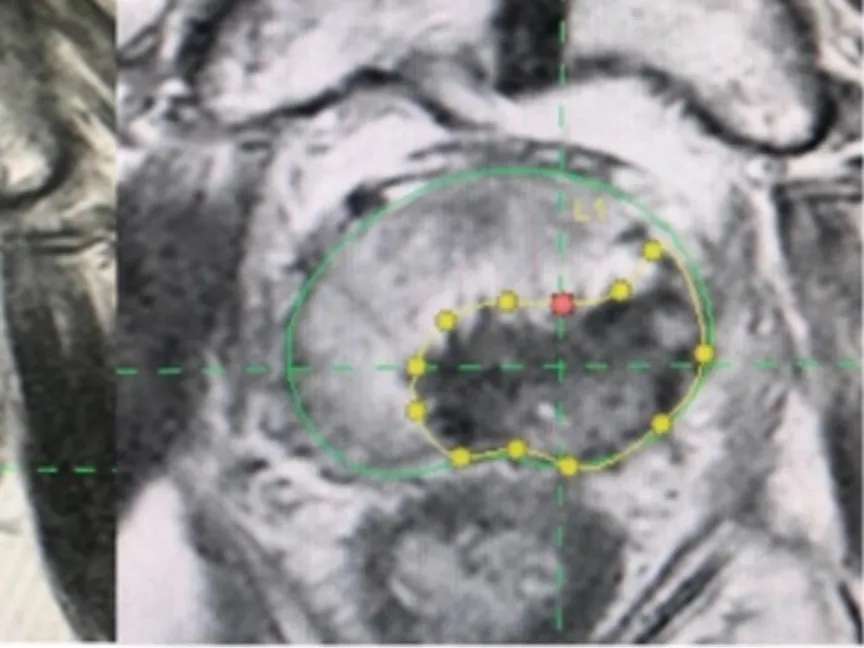

أجري العلاج تحت التخدير العام كإجراء ليوم واحد فقط. واعتمد التخطيط المسبق لمنطقة الاستئصال على صور الرنين المغناطيسي، مع إضافة هامش أمان لا يقل عن 5 ملليمتر حول الورم.

واستخدمت تقنيات توجيه مختلفة، شملت التوجيه الروبوتي في غالبية الحالات، أو دمج صور الأشعة المقطعية والرنين المغناطيسي مع الموجات فوق الصوتية.